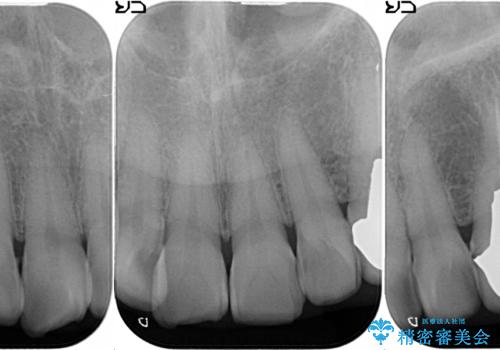

- 上下顎前歯部の見た目が気になるといらっしゃった方の症例です。

上顎は左4番から右4番までの8歯、下顎は左3番から右3番までの6歯、計14歯をオールセラミッククラウンにより補綴しました。

今回用いたオールセラミッククラウンはジルコニアフレームという白い素材の上にセラミックを盛っているため、審美性が非常に高いのが特徴です。

また、ジルコニアは人工ダイヤモンドの材料にも使われているほど高い強度を持っており、そのためオールセラミッククラウンは審美性だけでなく、奥歯やブリッジの補綴も可能とするクラウンです。